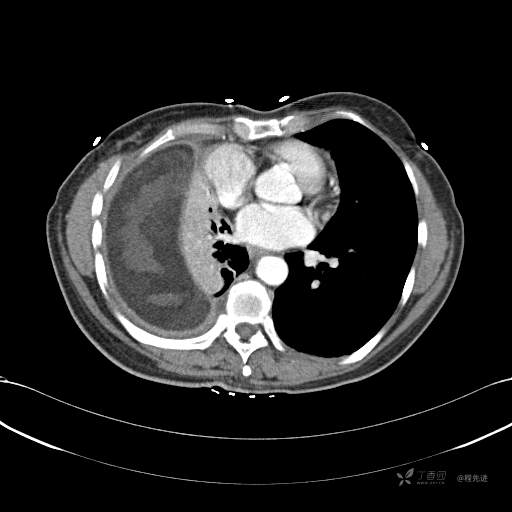

患者性别:女

患者年龄:51岁

简要病史:胸闷半年

肺淋巴管肌瘤病 (7)

乳糜胸 (8)